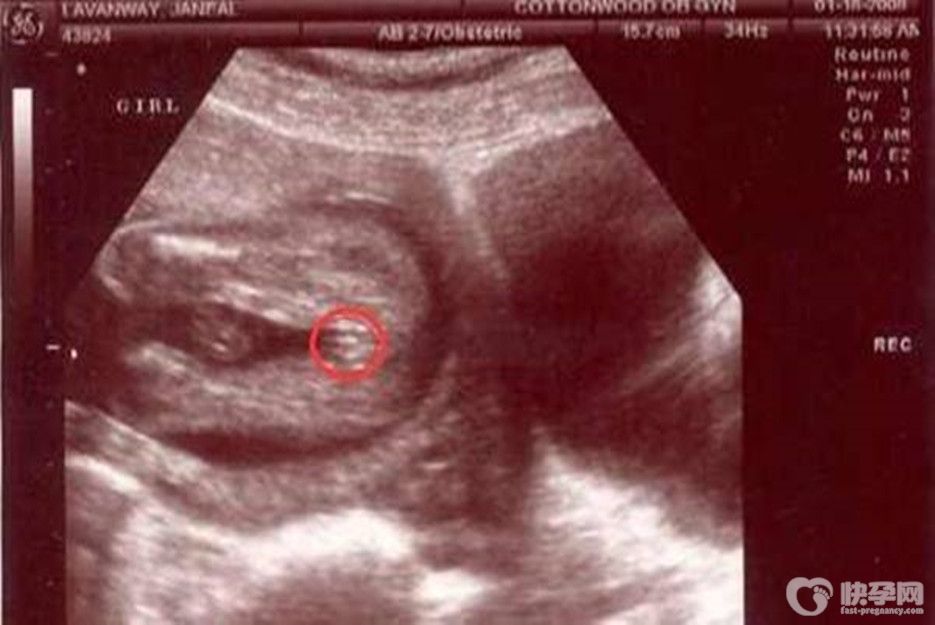

其实仔细观察就可以发现医生检查时的画面中会发现有小秘密,如果当时过错了,可以在四维单上的胎儿图片中看出来,如果在四维单的图片里能看到有凸出的东西,这个凸出的东西是有很大的奥秘的。这个凸点就是男孩的生殖器标志,圆圆的是DAN,圆圆的加小肠的就是全部生殖器官了,而女孩则是三条平行的直线,男孩与女孩生殖器部位图片区别很大的。